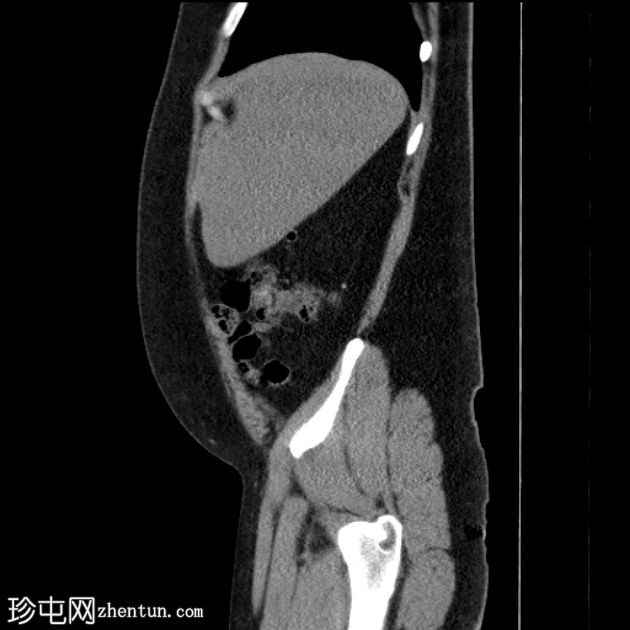

CT扫描

矢状位

平扫

肝下阑尾,无急性炎症改变。

左肾切除史。

未见右肾、输尿管或膀胱结石。无反压改变。

肝下阑尾是一种罕见的解剖变异,阑尾位于肝脏下方,通常是由于胚胎发育过程中肠旋转不全所致。

肝下阑尾炎是指阑尾和盲肠位于“肝下”位置时发生的炎症,如本例所示。

肝下阑尾炎在临床上常与肝胆疾病相似。